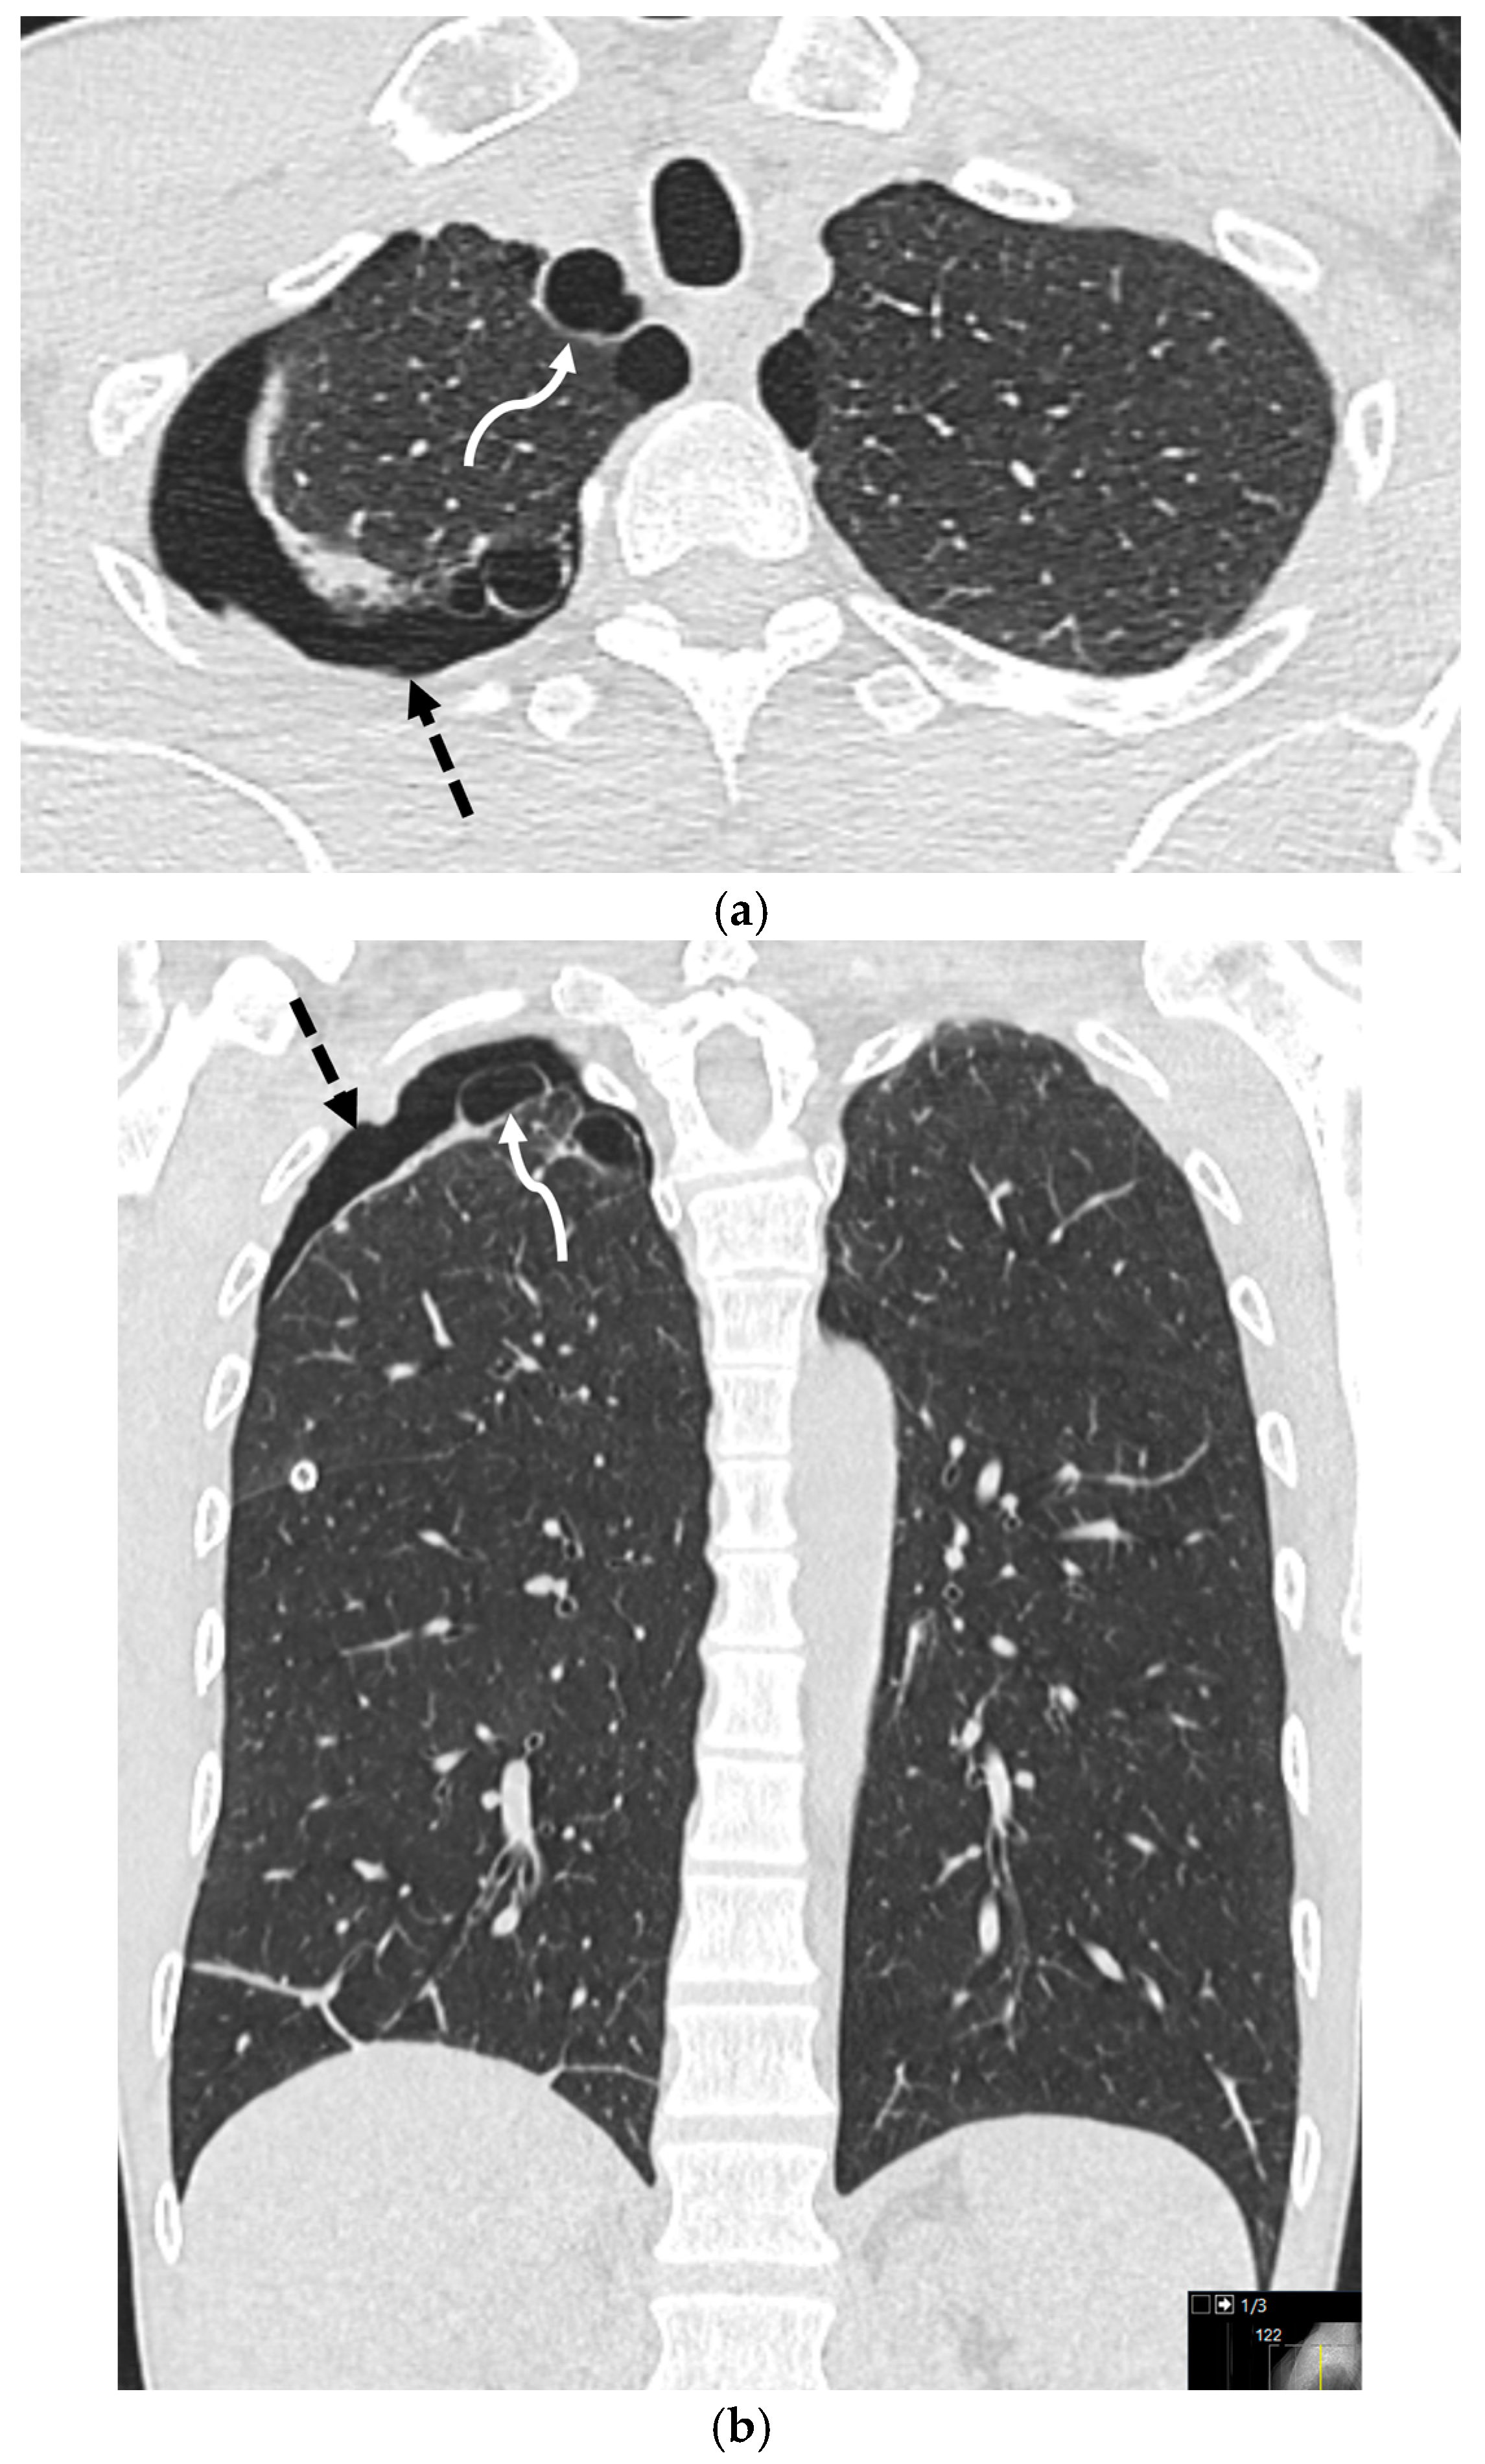

5.2.2. Cystic Fibrosis (CF)

5.2.3. Asthma